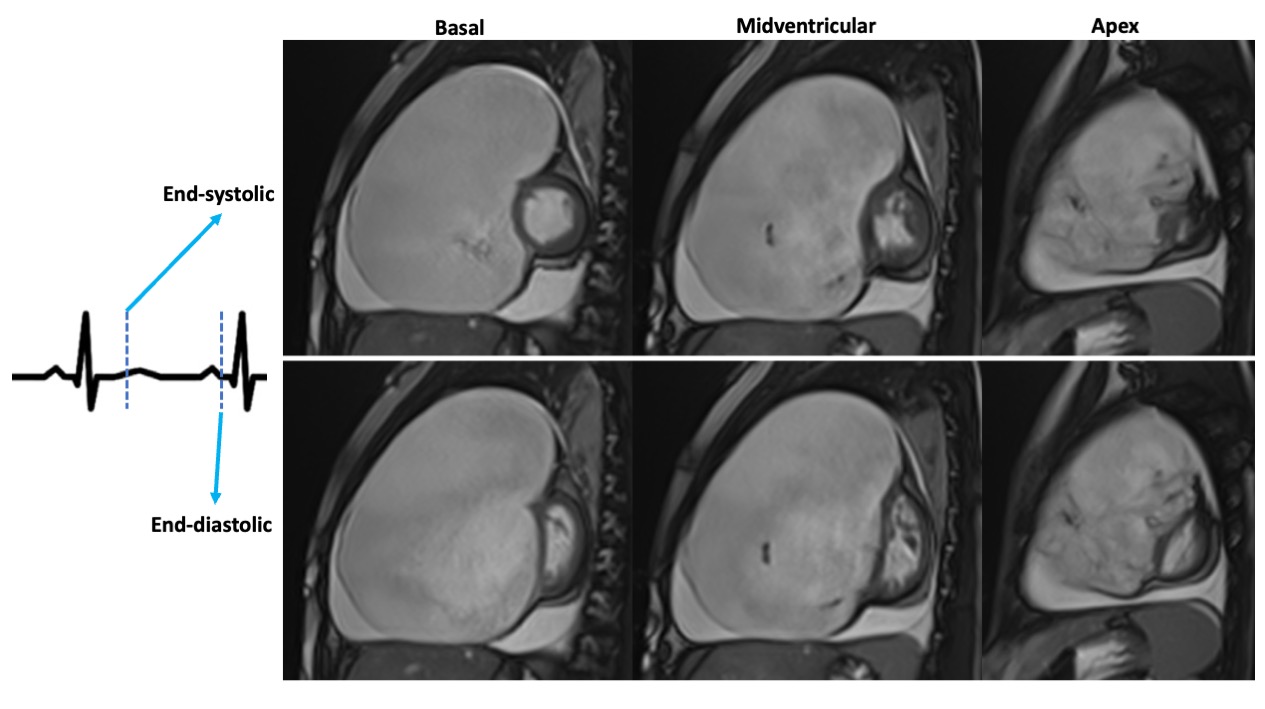

Figure 3. Cine bSSFP images in end-systolic (top row) and end-diastolic (bottom row) phases at basal, mid-ventricular, and apical levels of the short-axis view demonstrate a consistent diastolic leftward septal shift across all sections, producing a uniform “D-shape” configuration of the left ventricle and highlighting the extent of right ventricular volumetric overload.